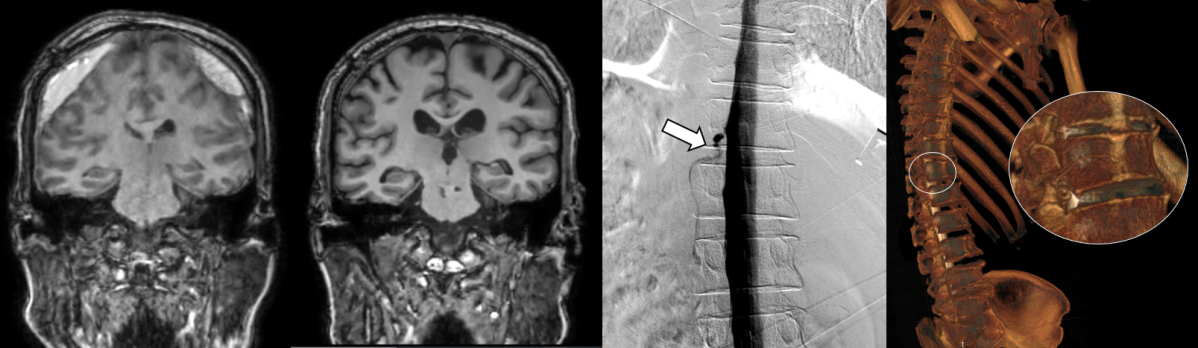

세브란스병원은 최근 디지털 감산 척수조영술(DSM)을 국내 최초로 도입해 이와 같은 기존 진단법의 한계를 극복했다. DSM은 척수에 조영제를 주입하고 모니터 화면으로 뇌척수액의 흐름을 실시간으로 확인할 수 있다. 이를 통해 뇌척수액이 새나가는 구멍을 정확하게 찾아낼 수 있게 됐다.

DSM과 더불어 세브란스병원이 함께 진행 중인 측위 컴퓨터단층촬영(CT) 척수 조영술까지, 모두 뇌척수액 정맥 누공을 진단할 수 있는 최신 기법이다. 신경과 전문의(주민경, 하우석 교수)와 신경외과 전문의(하윤 교수)가 긴밀히 협력하는 만큼 진단과 치료가 원스톱으로 가능하다.

이번에 세브란스병원을 찾은 환자들은 DSM 검사와 측위 CT 척수 조영술로 뇌척수가 새어나가는 부위를 정확히 진단‧치료받고, 뇌압을 회복했으며 경막하출혈도 사라졌다. 이에 따라 환자들이 보였던 인지기능 저하와 보행장애도 모두 호전됐다.